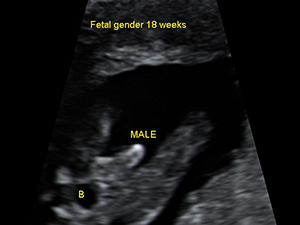

懷孕18週的男性胎兒性器官(箭咀)